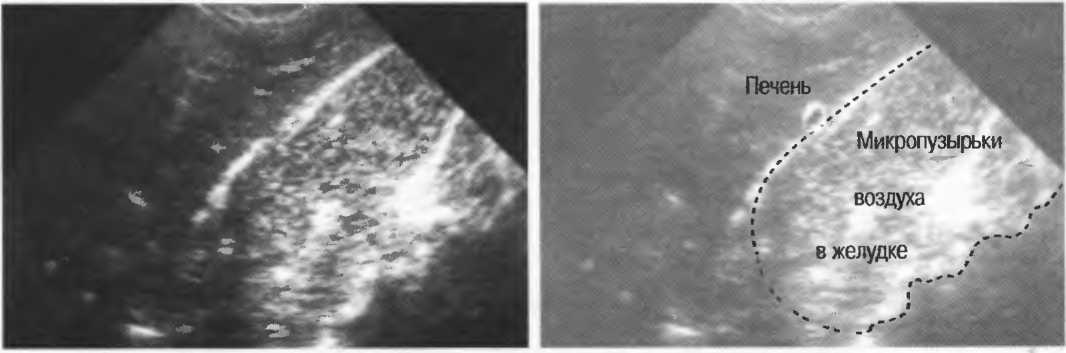

Акустическое усиление и акустическая тень

Чистые жидкости проводят ультразвуковой сигнал без существенного ослабления, поэтому отраженные эхосигналы, идущие от тканей, расположенных за жидкостью, обычно усилены (более яркие). Этот феномен известен как «акустическое усиление» (рис. 10а). Прием достаточного количества жидкости для заполнения желудка дает смещение кишечника, содержащего газ, и тем самым создает акустическое окно. Это особенно полезно для визуализации тела и хвоста поджелудочной железы.